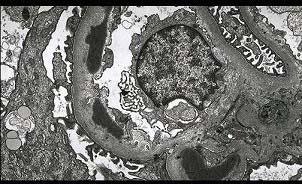

问题 阅读下列三张病理图片(图-1 Masson染色,图-2免疫荧光镜下IgG基膜内条带状沉积,图-3电镜下基底膜有电子致密物沉积,这些基底膜内的暗色的电子致密物沉积常融合成肋骨样)可诊断哪种病理类型 ( )

选项 A.局灶性节段性硬化 B.系膜增生性肾小球肾炎 C.膜性肾病 D.膜增生性肾小球性肾炎Ⅰ型 E.膜增生性肾小球性肾炎Ⅱ型

答案 E